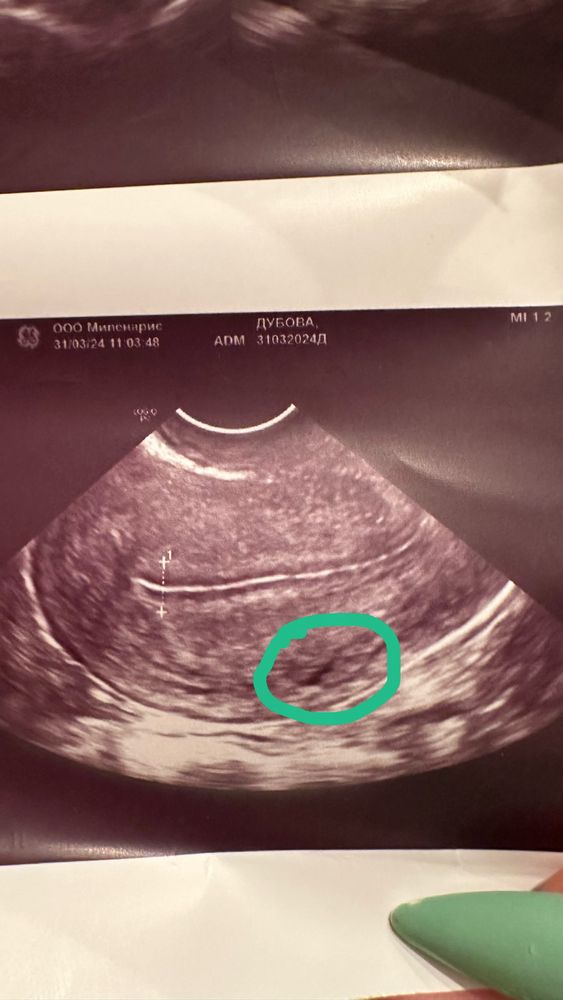

Точка на узи

В кружочке это сосуд, а белая полоса это эндометрий

Возможно какой то сосуд за телом матки